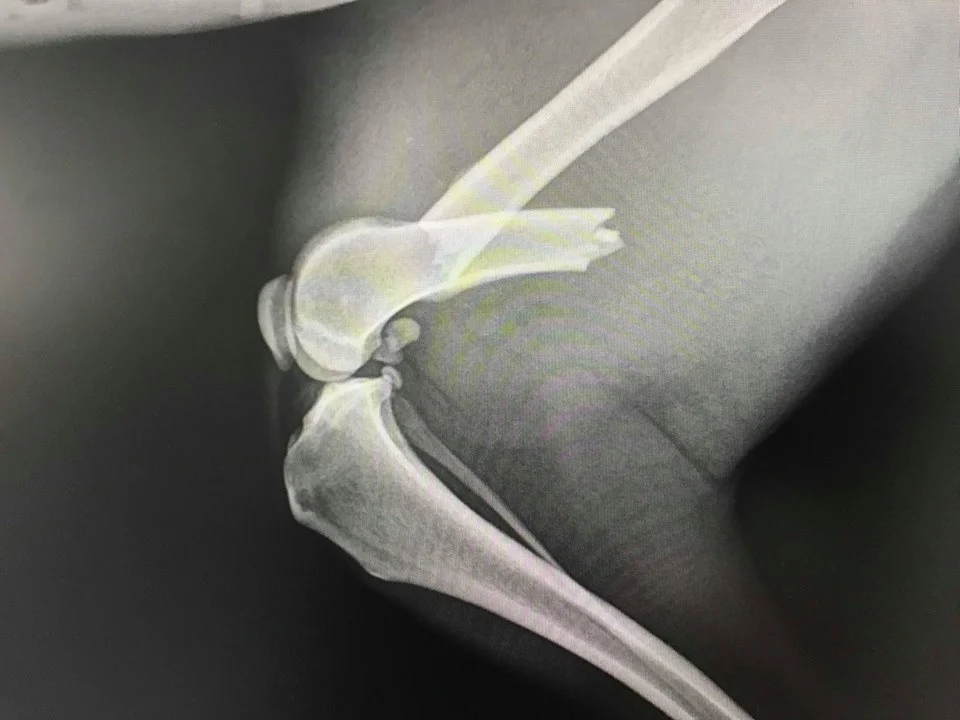

Bimba at vets when first rescued.

Break in leg